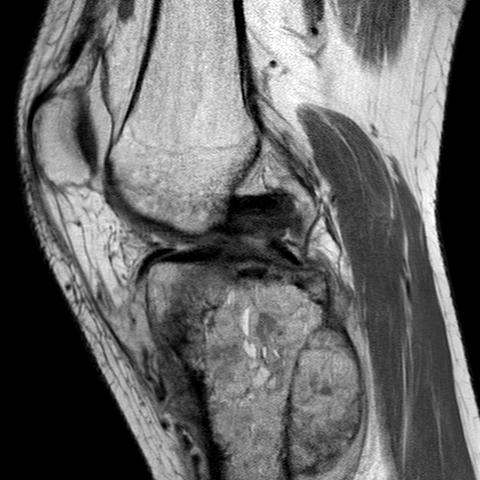

MRI

Evaluate

i) Soft tissue component

ii) Involvement of neurovascular bundle

iii) Marrow extent of tumour

- helpful in determining appropriate resection level

- satellite lesions - metastasis within reactive zone

iv) Identify skip lesions

- metastasis outside reactive zone

- sagittal and coronal images of the entire bone

v) Joint involvement